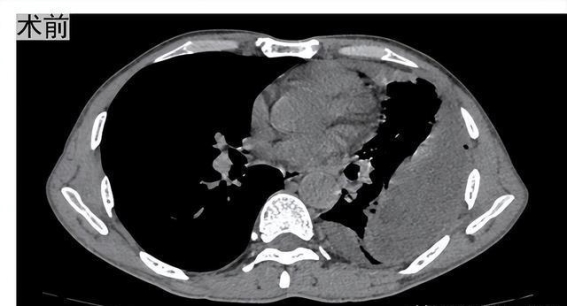

脓胸,这一病症往往在早期阶段不易引起患者足够的警觉,它通常表现为轻微的发热、咳嗽以及胸部不适,许多人会以为这只是普通的呼吸道感染,进而忽视了其潜在的严重性。脓胸···